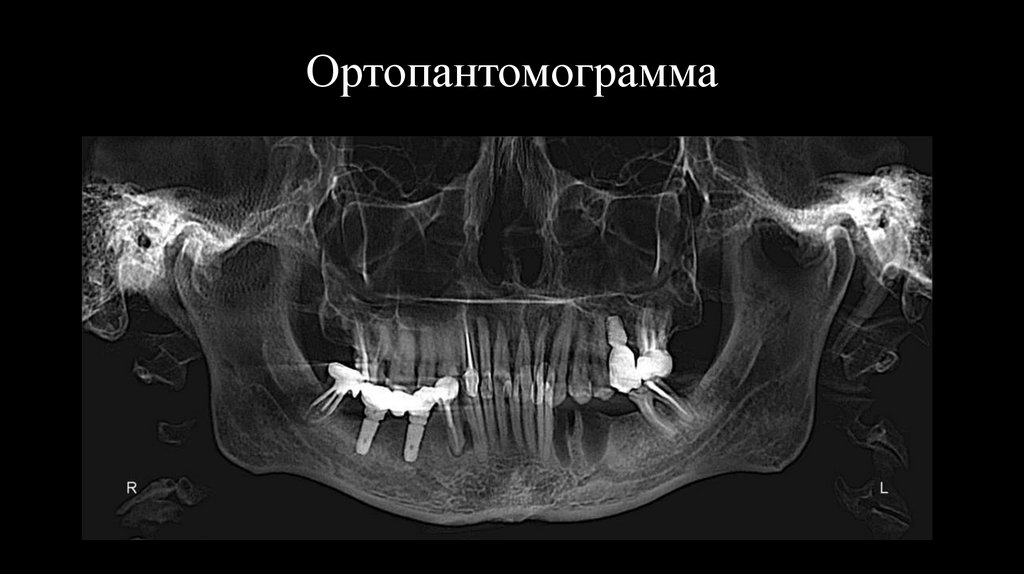

9. Ортопантомограмма

Отсутствуют зубы: 2.6, 3.7-3.4, 4.5-4.7.

Имплантаты: 2.6, 4.5, 4.7

Коронки на зубах: 2.6, 2.7, 4.4, 4.5-4.7